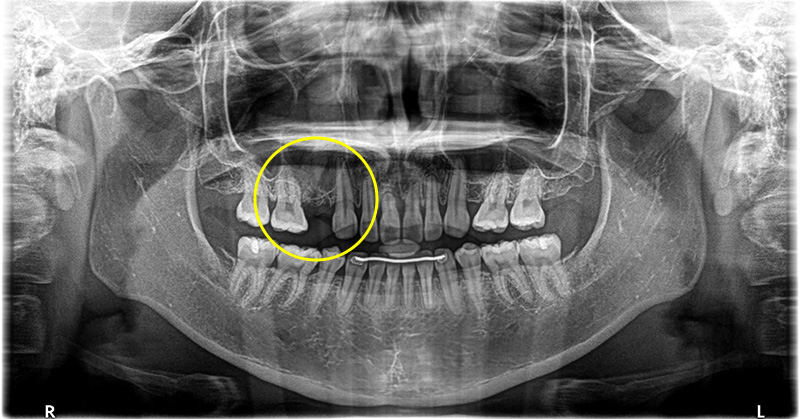

抜歯後の骨の治りが悪く、中に骨ができていない部分もあったため、小規模な骨造成も同時に行いました。

待機期間3ヶ月の間、歯がない事を無くす為に治療用義歯の作成を、希望されました。

インプラント治療の実施

2回法により施術を、行い、3ヶ月後には歯茎も綺麗に回復しておりました。